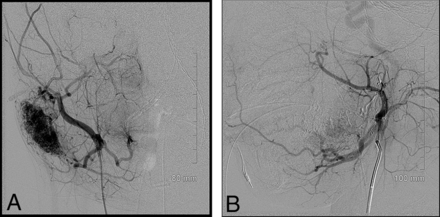

Our cases highlight several important points: noninvoluting congenital hemangiomas have the same angiographic appearance throughout the body. Figure 1 of a case involving an NICH in the anterior chest wall shows the same features as a facial NICH, including a discrete arterial-capillary web, homogeneous tumor blush, no arteriovenous shunting, and draining veins. This lesion was initially treated with QuadraSphere Microspheres (Merit Medical, South Jordan, Utah) (and did not significantly involute). The lesion was subsequently successfully treated with ethanol. Figure 2 highlights a right facial NICH with similar angiographic features. This lesion was successfully treated with polyvinyl alcohol particles, 45–120 μm. Markedly enlarged draining veins are noted in this example.

Right external carotid artery injection of a right facial NICH. Again, there is a discrete angiographic appearance involving an arteriocapillary web, no arteriovenous shunting, and identifiable draining veins. This lesion was treated successfully with polyvinyl alcohol particles.